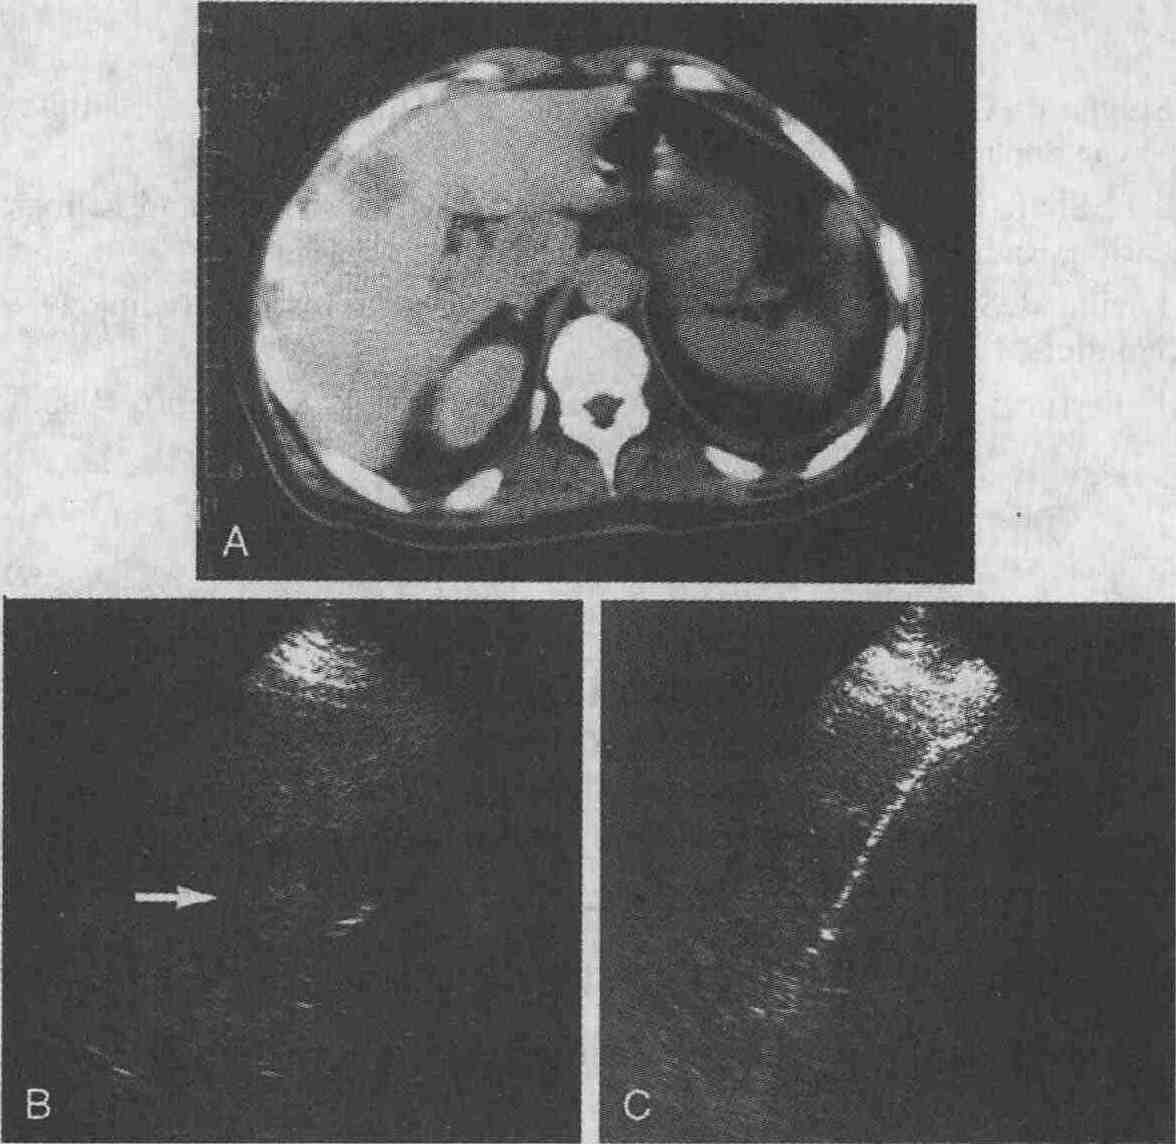

Метастазы рака ободочной кишки в печень.

А. При выполнении КТ печени с использованием контрастных веществ определяется

участокткани со сниженной плотностью диаметром 3 см. В. При УЗИ в печени

определяется объемное гипоэхогенное образование (стрелка). С. При ультразвуковом

сканировании видна биопсийная игла (снимок сделан во время выполнения биопсии,

проводимой под контролем УЗИ)